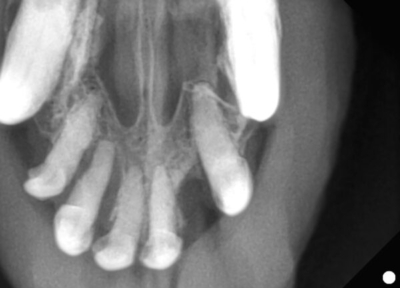

上顎切歯

上顎の切歯のレントゲン

黄色斜線部分が歯の周りの骨が溶けてしまったところ。

このようにひとつひとつの歯を評価していきます。